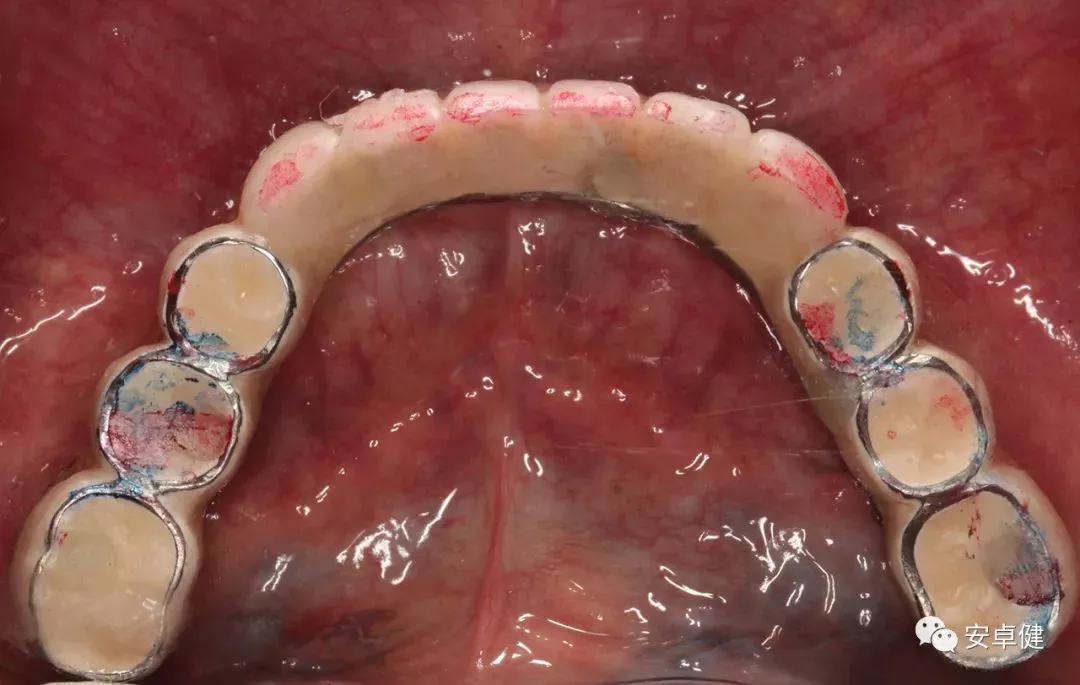

• 制作最终修复体蜡型,分别于架及口内试戴检查其外形及咬合;

最终修复体蜡型上架正面观

最终修复体蜡型上侧面观

试戴最终修复体蜡型正面照

试戴最终修复体蜡型侧面照

试戴最终修复体蜡型合面照

• 完成最终修复体制作。

▷ 永久修复

• 于口内试戴原厂纯钛切削一体式桥架,并检查前牙排蜡外形及后牙咬合关系;